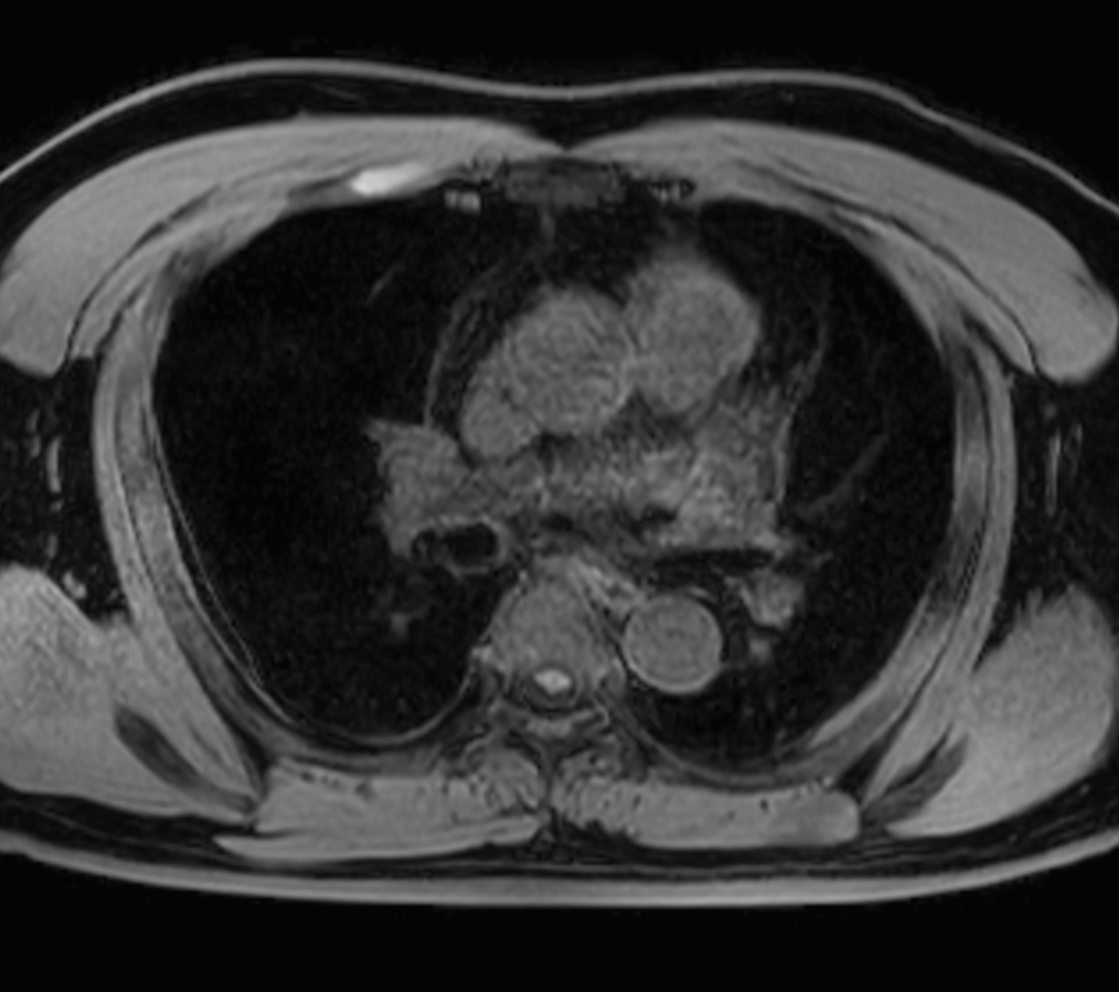

Axial MultiVane XD - T2w SPIR